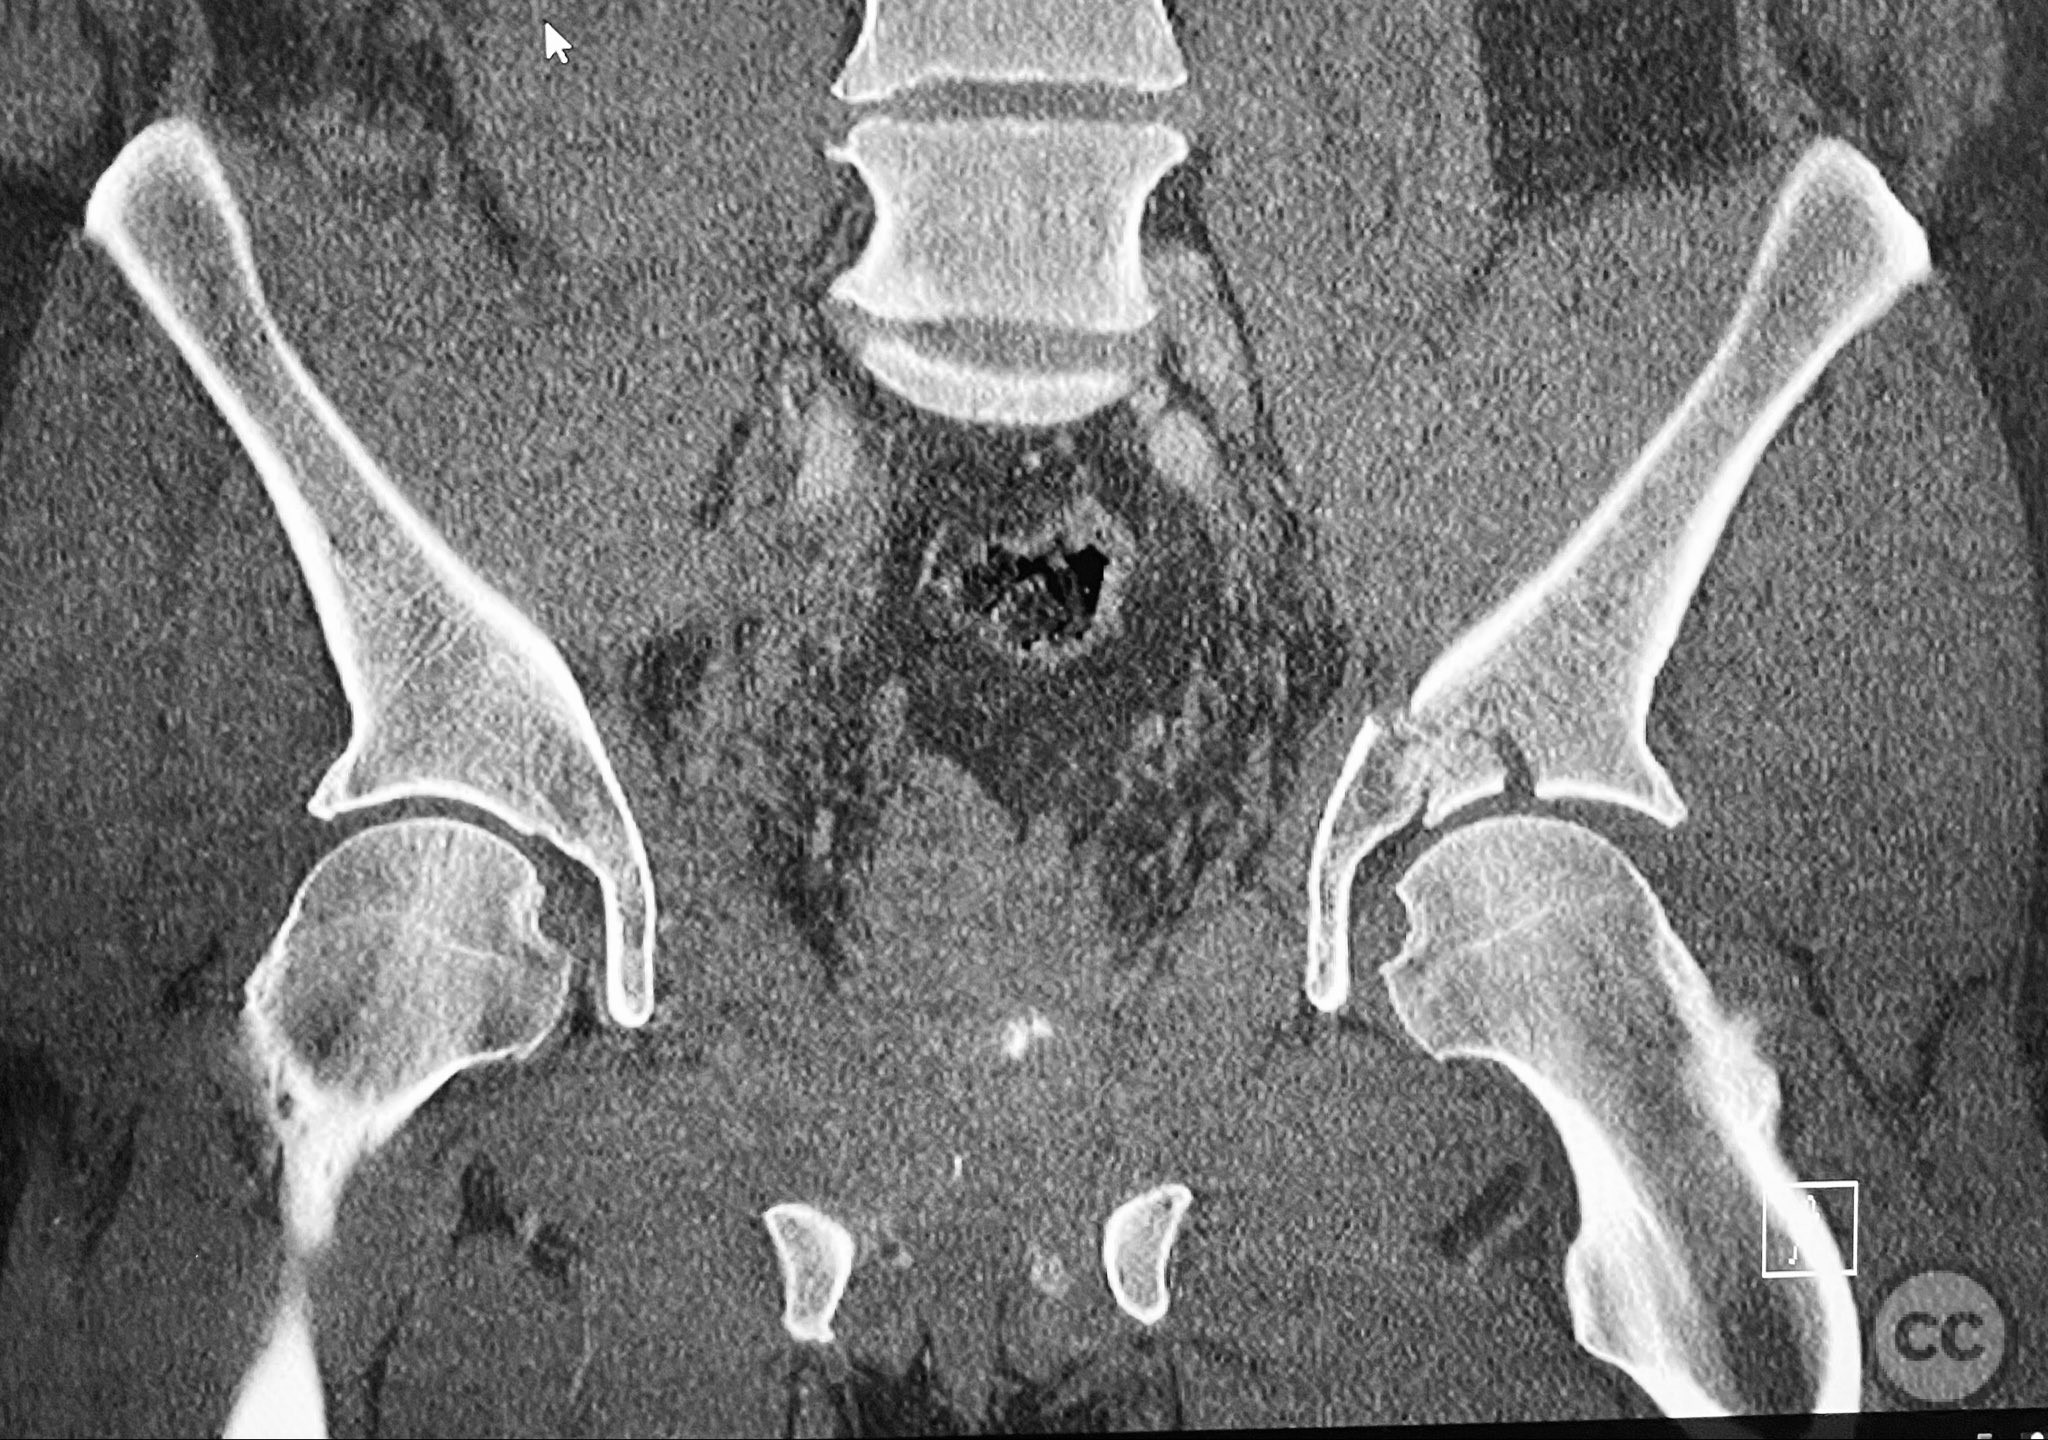

Clinical and radiological findings:  Adult male with a closed, comminuted left femoral shaft fracture and complex pelvic ring injury. Initial imaging demonstrated bilateral sacroiliac (SI) joint disruptions and a left-sided transtectal transverse acetabular fracture (Letournel-Judet: transverse type), with the fracture line exiting through the posterior wall region but without a discrete posterior wall fragment. The femoral head was displaced caudally, following the unstable distal acetabular segment, resulting in loss of congruency with the intact acetabular dome. There was also a symphyseal disruption. No associated abdominal, visceral, thoracic, cranial, or other injuries were present. Application of a circumferential pelvic binder resulted in visible changes in pelvic alignment on imaging. AO/OTA Classification: - Pelvic ring: 61-C1.3 (bilateral SI joint disruption, complete instability) - Acetabulum: 62-B1 (transverse fracture) - Femur: 32-C3 (comminuted diaphyseal fracture)

Planning remarks:  The preoperative plan involved staged management: initial resuscitation and provisional stabilization with a circumferential pelvic binder, followed by operative reduction and fixation of the pelvic ring using an anterior two-pin external fixator for SI joint compression and reduction, percutaneous iliosacral (IS) and transsacral (TS) screw fixation, and subsequent intramedullary nailing of the femur. Definitive acetabular fixation was planned via a posterior Kocher-Langenbeck approach in the prone position.